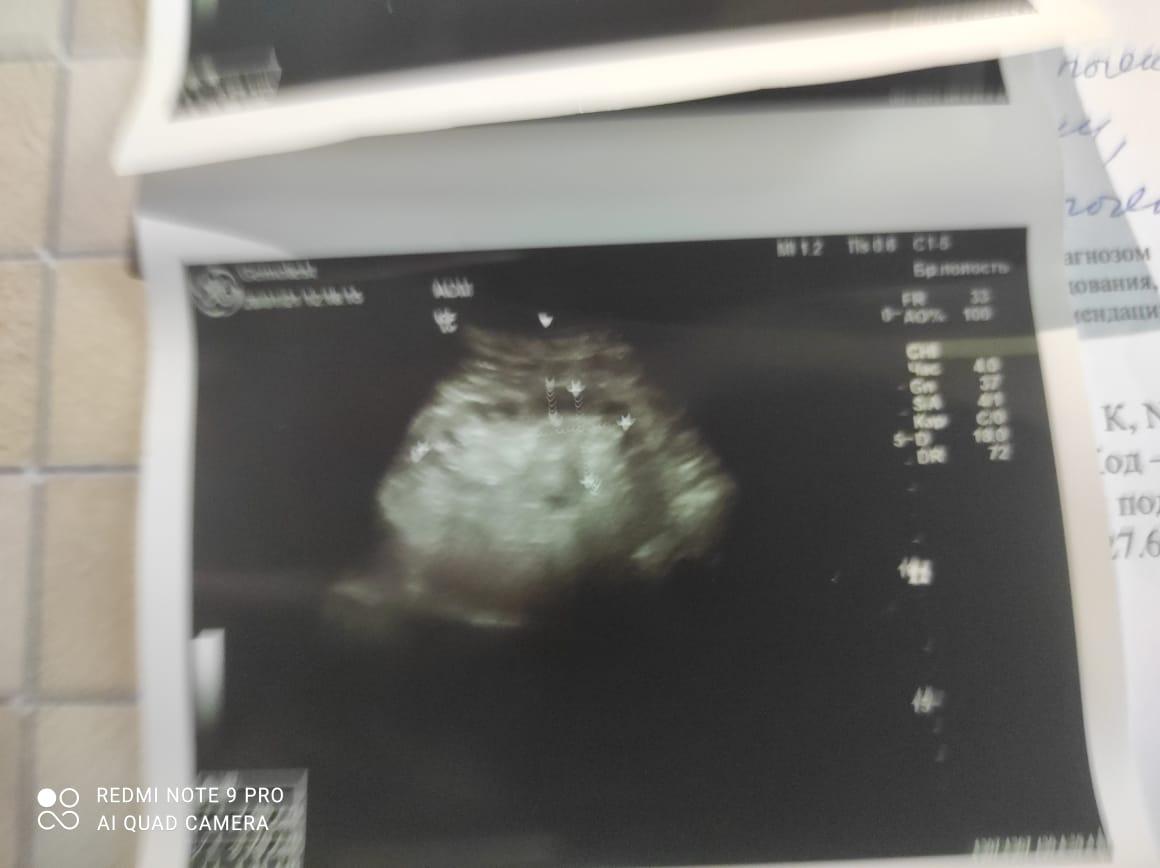

Здравствуйте! При наличии коралловидного камня правой почки(заключение УЗИ), можно предположить причиной боли нарушение уродинамики верхних мочевых путей), что, однако, не подтверждается результатами УЗИ почек( ЧЛС не расширена). Другая, наиболее вероятная возможная причина "боли в боку" - может быть патология опорнодвигательного аппарата. Необходимо проконсультироваться с неврологом и урологом очно, и согласовать возможность применения противовоспалительных, обезболивающих и спазмолитических препаратов - как первый шаг. В дальнейшем необходимо планировать возможное дальнейшее обследование и лечение. Удачи!